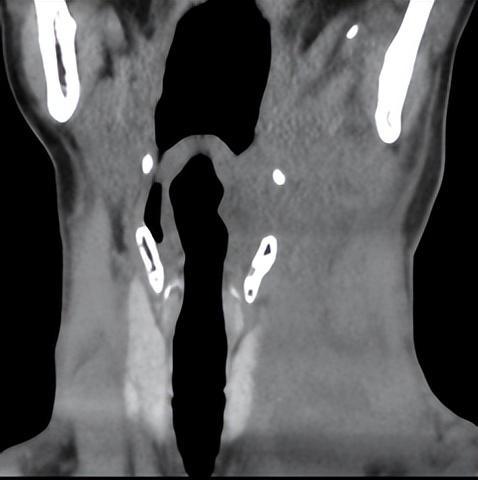

(入院时颈部CT病情)

直觉提示病情重,立即予以加强抗炎,消肿,全身能量营养支持、雾化及中药外敷内服等治疗,与此同时告知患者、家属目前病情严重程度及风险性,然而,患者及家属仍未意识到病情凶险及致命性。

主管医生随即备气管切开包于床旁。一旦呼吸困难,随时做好气管切开准备,并叮嘱护理团队加强护理巡视。